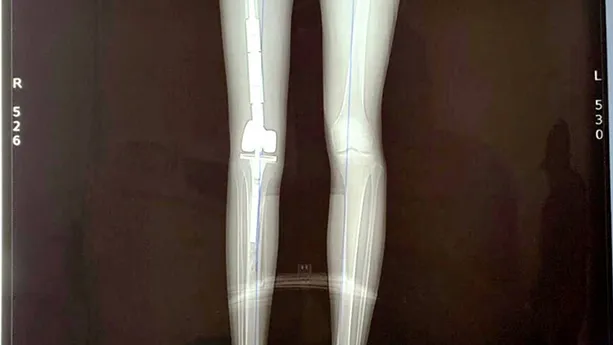

Sau khi được chuyển tới Bệnh viện K, qua thăm khám và chụp chiếu, các bác sĩ chẩn đoán bệnh nhân H. bị ung thư xương. Ngay lập tức, bệnh nhân được truyền hóa chất tiền phẫu 3 đợt. Bệnh nhân đáp ứng hóa chất tốt, sau đó được phẫu thuật cắt bỏ đoạn đầu dưới xương đùi phải và tiếp tục truyền hóa chất hậu phẫu 6 đợt. Tuy nhiên, sau khi điều trị hóa chất hậu phẫu, vùng chỏm xương đùi có vùng tổn thương mới. Các bác sĩ quyết định phẫu thuật tháo bỏ toàn bộ xương đùi, thay thế bằng xương đùi nhân tạo cho bệnh nhân H.

Ê kíp phẫu thuật gồm các chuyên gia của Bệnh viện K, Bệnh viện Đại học Y Hà Nội và Bệnh viện Xanh Pôn đã thực hiện thành công ca phẫu thuật thay toàn bộ xương đùi bên phải cho bệnh nhân H. Đồng thời tiến hành thay khớp háng và khớp gối toàn phần, khâu phục hồi lại các điểm bám gân cơ.

5 ngày sau mổ, vết thương đã ổn định. Đến nay, các chi, khớp của bệnh nhân H. đã cử động được. Theo các bác sĩ, ca phẫu thuật cắt bỏ tổn thương ung thư và thay toàn bộ xương đùi kim loại cho bệnh nhân H. là ca phẫu thuật được thực hiện lần đầu tiên tại Việt Nam, đã mở ra hy vọng bảo tồn chi thể cho các bệnh nhân bị ung thư xương nói chung, ung thư xương đùi nói riêng.